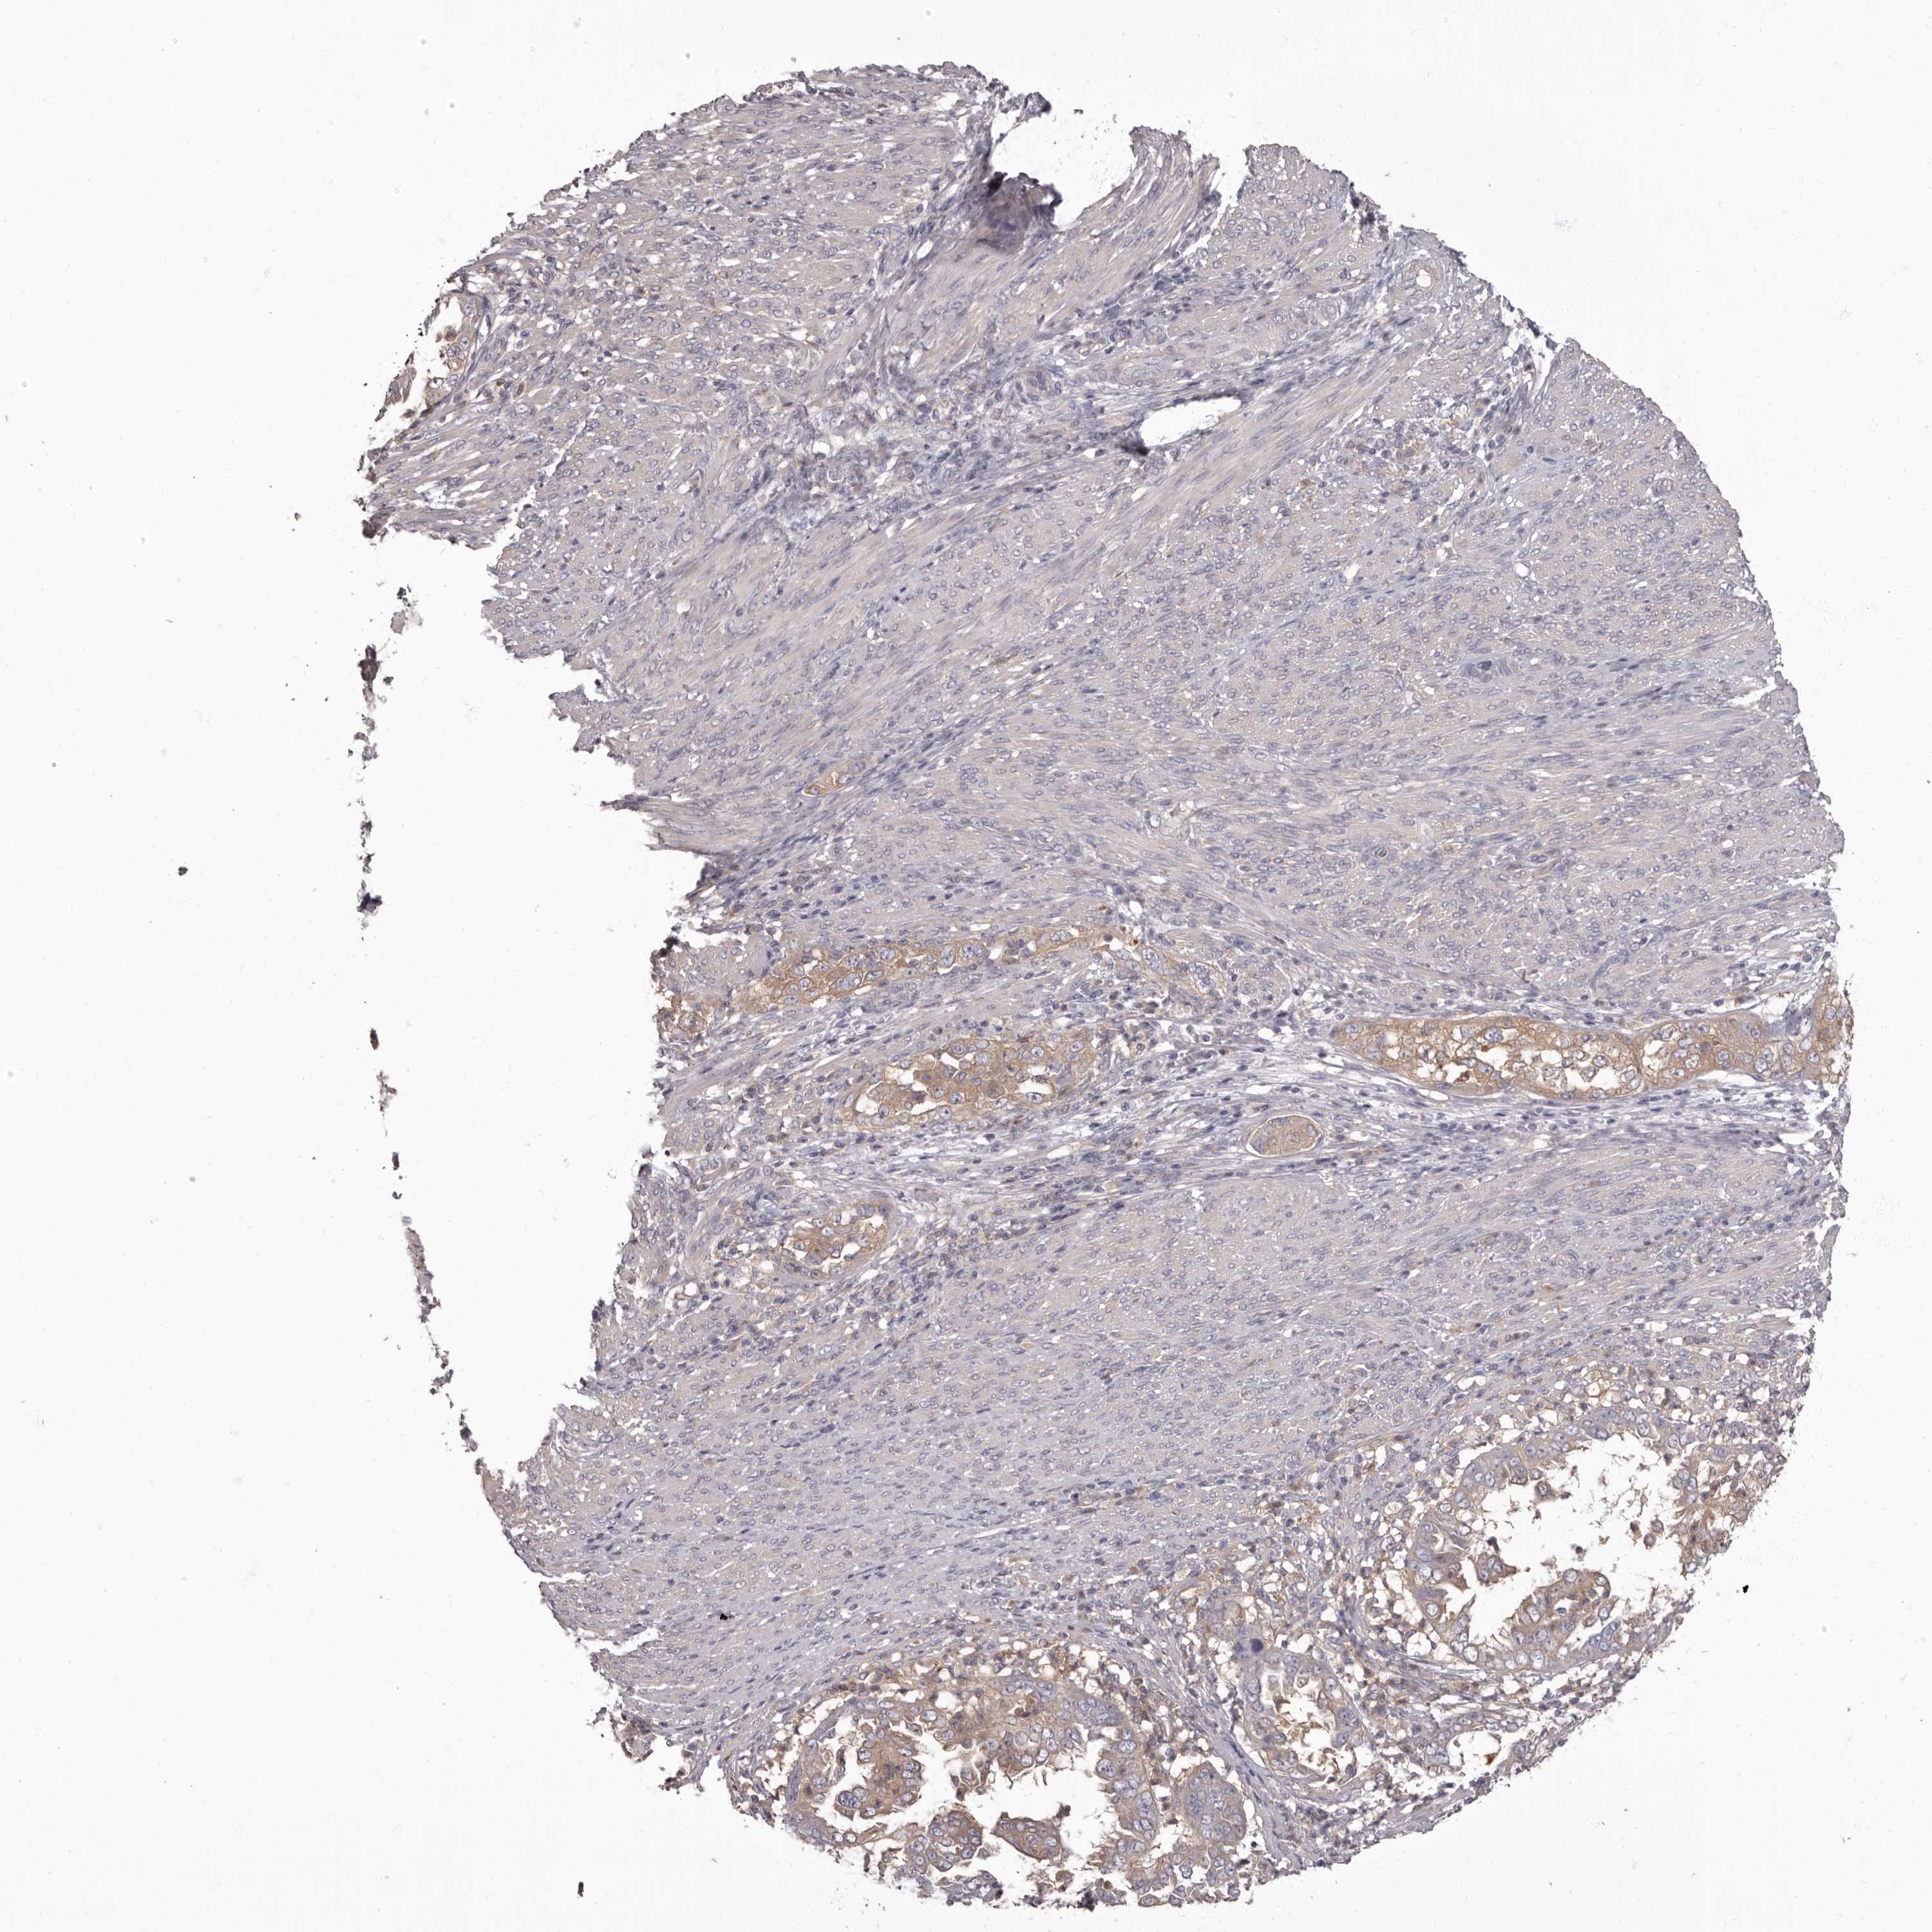

ENDOMETRIAL CANCER - Protein expressioni

A mouse-over function shows sample information and annotation data. Click on an image to view it in a full screen mode. Samples can be filtered based on level of antibody staining by selecting one or several of the following categories: high, medium, low and not detected. The assay and annotation is described here.

Note that samples used for immunohistochemistry by the Human Protein Atlas do not correspond to samples in the TCGA dataset.

Antibody stainingi

Antibody staining in the annotated cell types in the current human tissue is reported as not detected, low, medium, or high, based on conventional immunohistochemistry profiling in selected tissues. This score is based on the combination of the staining intensity and fraction of stained cells.

Each image is clickable and will lead to virtual microscopy that enables deeper exploration of all samples and also displays staining intensity scores, fraction scores and subcellular localization as well as patient and tissue information for each sample.

Antibody HPA029700

Antibody HPA029701

Antibody HPA029702

Antibody HPA029703

Staining

High

Medium

Low

Not detected

Intensity

Strong

Moderate

Weak

Negative

Quantity

>75%

75%-25%

<25%

None

Location

Nuclear

Cytoplasmic/membranous

Cytoplasmic/membranous,nuclear

Adenocarcinoma, NOS

Adenocarcinoma, metastatic, NOS